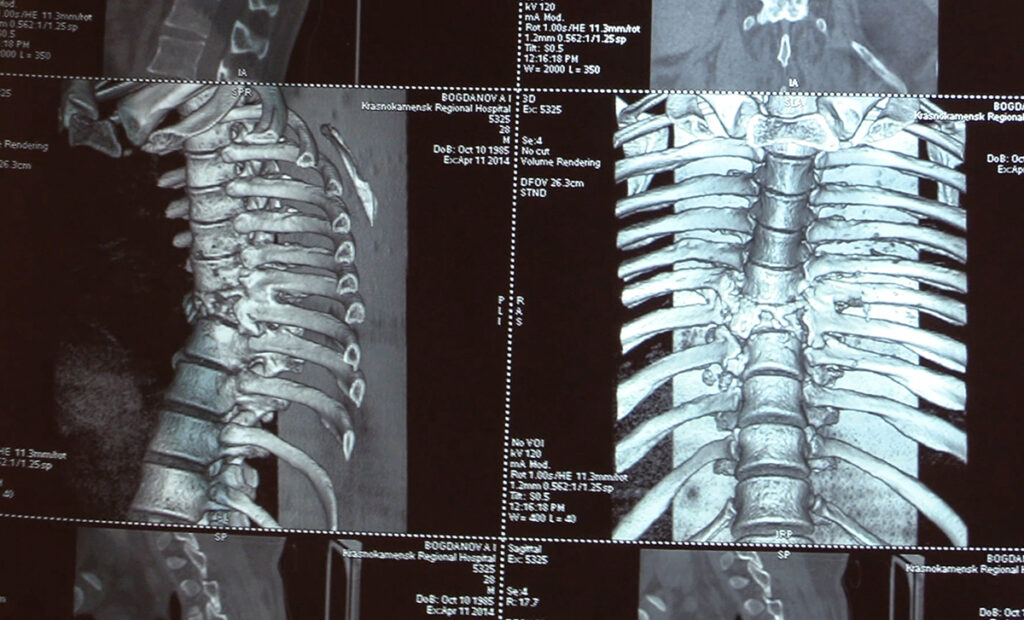

Авария на дороге. И перелом позвоночника. Срочную операцию практически в «полевых условиях» ему делал нейрохирург из санавиации. Сделал, что мог. Но разрыв спинного мозга было не исправить.

Ниже груди Анатолий с тех пор ничего не чувствует. Сидеть сам не может. Родители надевают на него специальный корсет, пристегивают к коляске – тогда он «в рабочем положении».